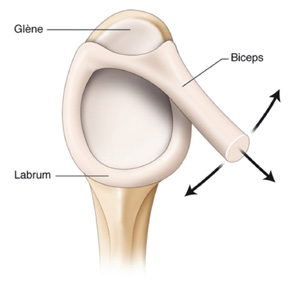

¿QUÉ ES LA LESIÓN SLAP?:

La lesión SLAP es la afección de la inserción o anclaje del tendón de la porción larga del bíceps en el hueso glenoides que forma parte de la articulación del hombro. Esto genera mucho dolor y limitación para movimientos del hombro. puede percibirse un resalto o chasquido en algunos casos.